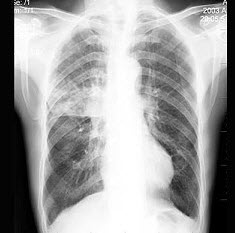

13、单项选择题

男,52岁,从事矿井工作32年,近几年出现气喘,呼吸困难,胸片如图,其最可能的诊断为()

A.双肺浸润性结核

B.双肺真菌感染

C.两肺弥漫性间质性肺炎

D.两肺弥漫性纤维化

E.矽肺